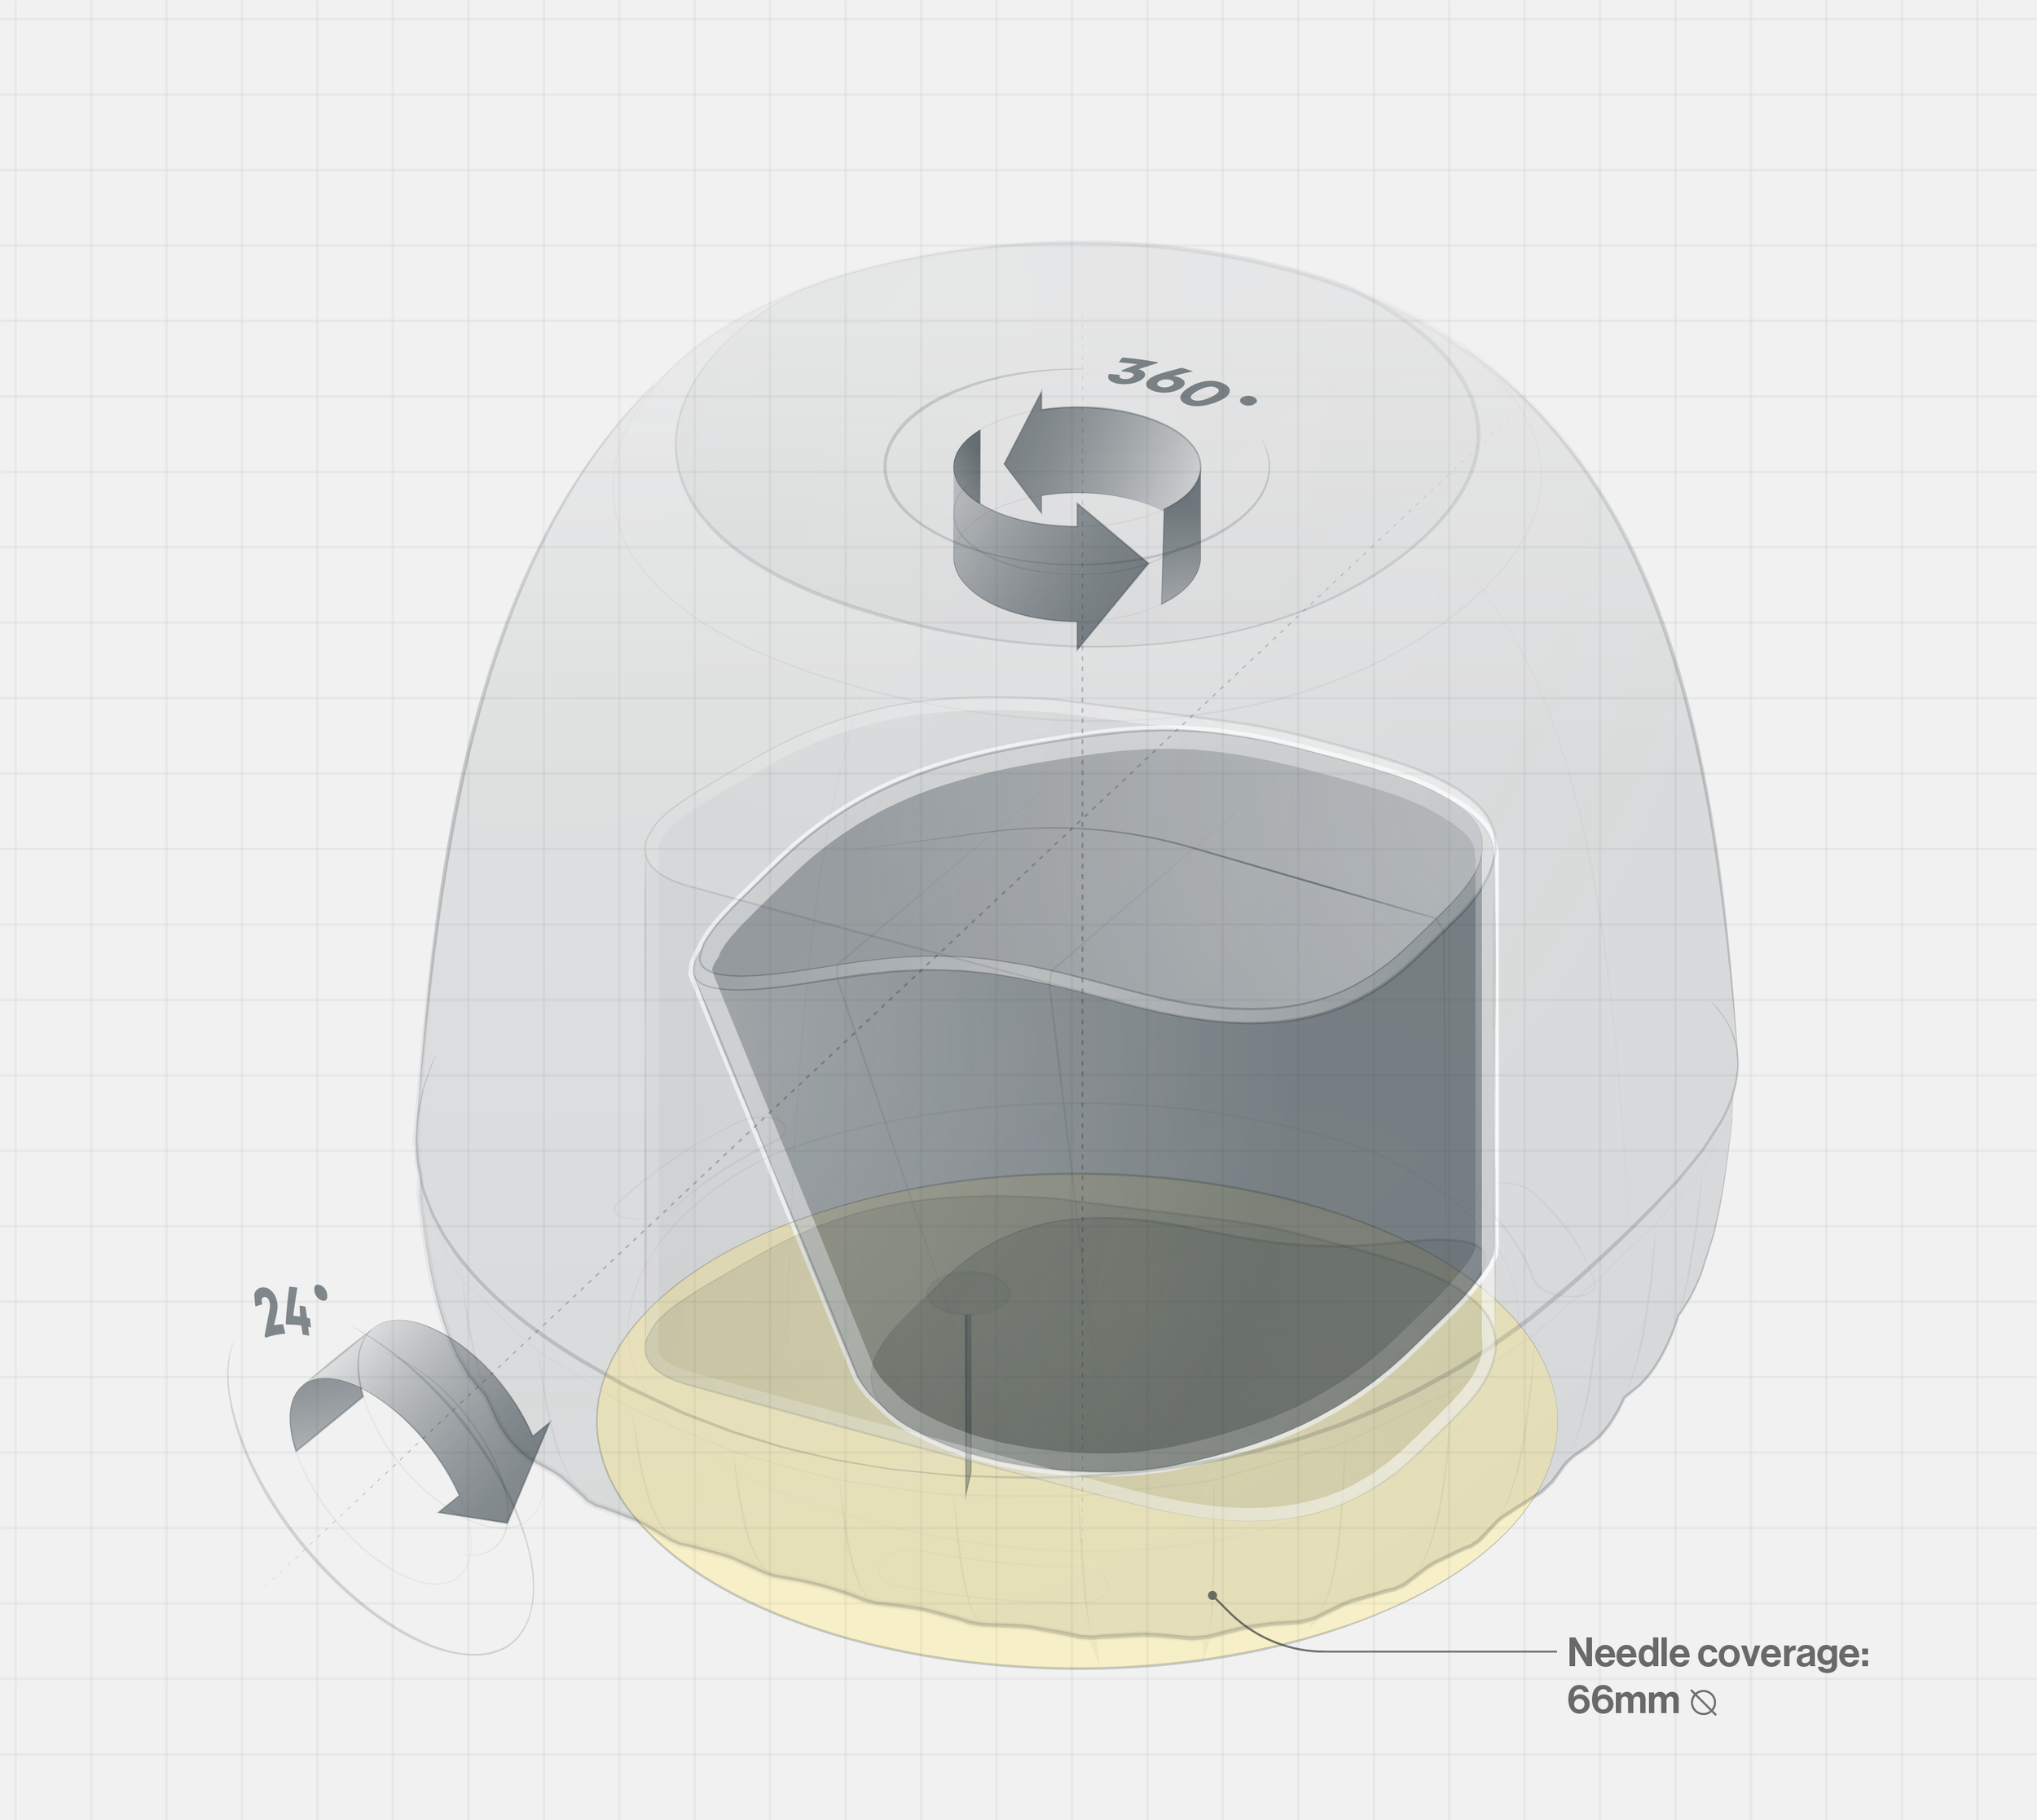

Ballad is a smart insulin pen that helps visually impaired diabetics self-administer insulin confidently. High-contrast touchpoints, a connected app with an enlarged dose display, and replaceable cartridges simplify treatment and promote independence while reducing plastic waste. (Cambridge Consultants)